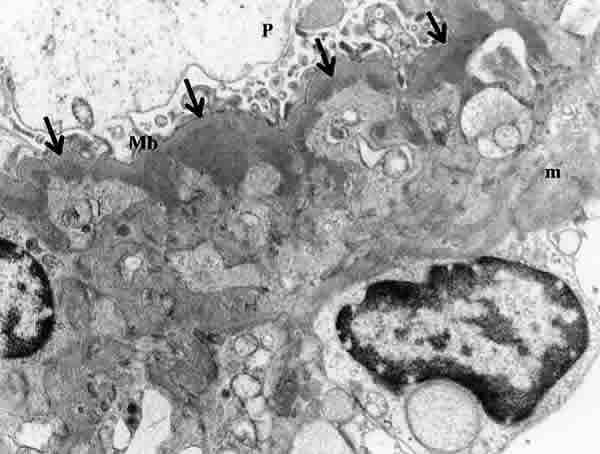

Fig. 6. Glomerulonefritis focal segmentaria con hialinosis. Depósitos electrón densos subendoteliales en un foco de hialinosis.